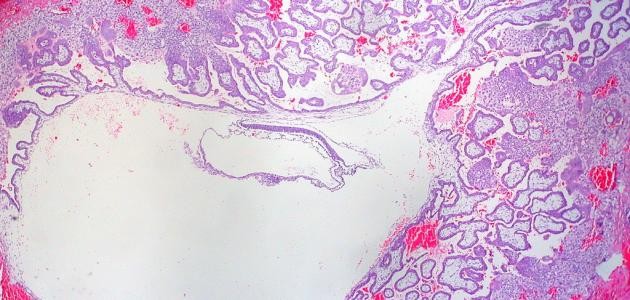

يُعرف هرمون الحمل علمياً بموجهة الغدد التناسلية المشيمائية (بالإنجليزية: Human Chorionic Gonadotropin)، واختصاراً hCG، ويتمّ إنتاج هذا الهرمون من قبل الخلايا المكوّنة للمشيمة (بالإنجليزية: Placenta) التي تُمثّل النسيج المسؤول عن تغذية البويضة المخصبة بعد انغراسها في بطانة الرحم، ويمكن الكشف عن وجود هذا الهرمون في الدم بعد مرور 11 يوماً من وقت حدوث الحمل، بينما يمكن الكشف عنه بفحص البول بعد مرور 12-14 يوماً على وقت حدوث الحمل، وفي الحقيقة يبدأ هرمون الحمل بالتضاعف من وقت حدوث الحمل كل 48-72 ساعة ليصل أعلى مستوياته في الفترة الممتدة بين الأسبوع الثامن والأسبوع الحادي عشر من الحمل، وفي الحقيقة بتقدم الحمل يحتاج هرمون الحمل فترة تُقدّر بـ 96 ساعة لترتفع مستوياته، ثمّ يبدأ بالانخفاض بشكلٍ تدريجيّ ثمّ ليثبت على معدّل مقبول، ويُقاس هرمون الحمل بوحدة ملي وحدة دولية/ملليتر، وتجدر الإشارة إلى أنّ هناك نوعين من الفحوصات التي تكشف عن هرمون الحمل، الأول يُعرف بفحص هرمون الحمل النوعيّ (بالإنجليزية: Qualitative hCG test) والذي يكشف عن وجود الحمل أو ينفيه دون القدرة على الكشف عن معدله، في حين يتمّ قياس معدل هرمون الحمل من خلال الفحص الذي يُعرف بفحص هرمون الحمل الكميّ (بالإنجليزية: Quantitative beta-hCG test)، ويُطلب هذا الفحص في بداية الحمل للتأكد من وجود الحمل وسلامته، وبعد ذلك غالباً لا يُطلب قياسه إلا في حال معاناة الحامل من بعض المشاكل المرتبطة بالحمل، مثل النزف، أو المغص الشديد، أو الإجهاض، أو غير ذلك.